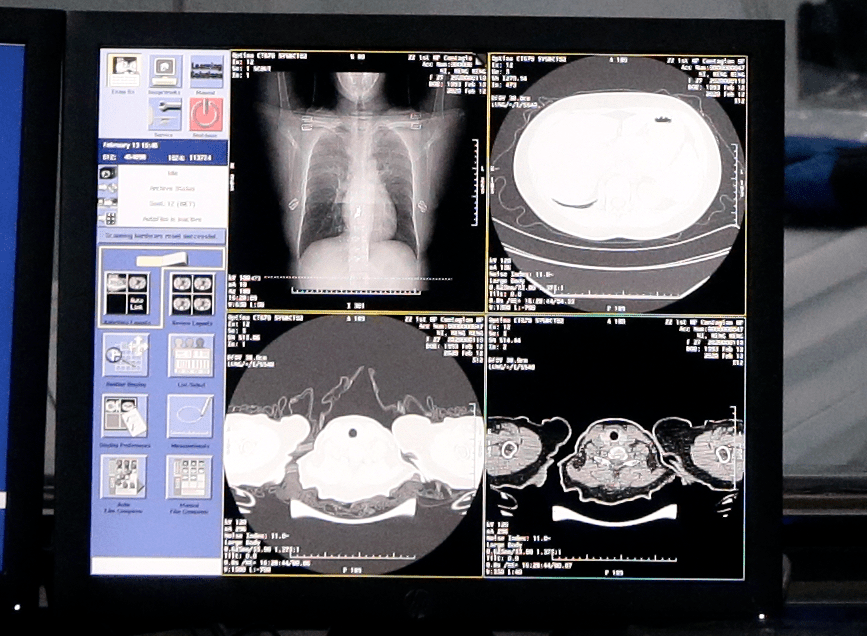

阿里巴巴达摩院AI自动识别新冠肺炎病例CT胸片

2020年,中国科技馆收藏了国内首张利用AI识别新冠肺炎的CT影像——阿里巴巴达摩院AI抗疫作品。如今这一作品静静躺于中国科技馆数字馆藏中。

国内,肺炎患者的阶段性暴涨也一度让不同科室的医护人员聚集到呼吸科。人工智能影像辅助诊断方法帮助医生们提升了阅片时的工作效率——中国科学技术馆相关数据,AI智能影像识别进入新冠肺炎病毒医学影像筛查后,病例CT影像数据识别时间被压缩到20秒以内,最终识别准确率达90%以上。

肺炎患者从入院到出院一般需要拍摄四次左右的CT影像,在传统的CT影像量化评估过程中,每拍摄一次CT,医护人员都需要手动勾画三四百张的CT影像,通过肺叶计数或肺段计数来统计肺叶、肺段的病变范围,从而评估新冠肺炎的严重程度,这一过程耗时长达五六个小时。但当AI遇上疑似病例,会自动发起对可疑区域的重点识别,自动统计各个肺部解剖结构中肺炎区域的占比,形成量化数据提供医生,缩短评估和阅片时长。